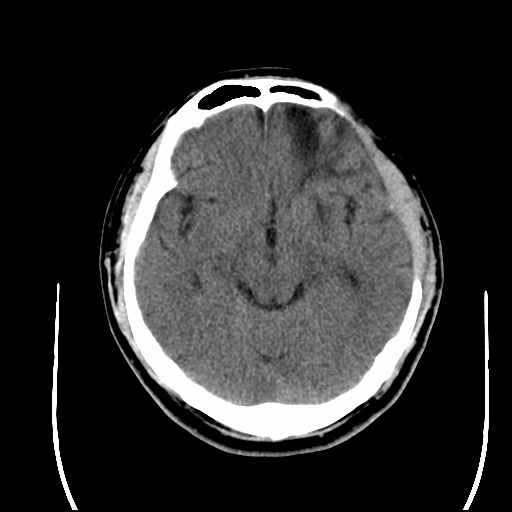

25岁的男青年小董,在2024年4月的一天,无明显诱因突发剧烈头痛后很快进入昏迷状态,就诊于首都医科大学附属北京潞河医院急诊神经外科,头颅CT检查显示:左侧额叶大量出血。入院后,急诊进行脑血管造影,发现左侧颅底的硬脑膜动静脉瘘,颅底脑膜广泛供血。考虑到硬脑膜动静脉瘘导致大量出血,病情复杂,且双侧瞳孔散大,脑疝形成。王浩主任医师、杨俊副主任医师迅速判断病情后,认为需要急诊行开颅探查血肿清除去骨瓣减压术+硬脑膜动静脉瘘切除术。在麻醉科的积极配合下,手术团队成功清除脑内血肿,术中发现硬脑膜动静脉瘘复杂予以切除,同时行去骨瓣减压术,解除脑疝,手术历时6个小时,最终顺利结束。小董被平稳转运回重症监护病房,术后经过科室医护团队的精心治疗与护理,小董出院了。出院时小董神清语利,双侧肢体肌力正常,无明显神经功能障碍,生活完全自理,出院前进行CTA评估硬脑膜动静脉瘘有部分残留,拟3个月后回医院进行颅骨修补手术时一并切除。

急诊手术后